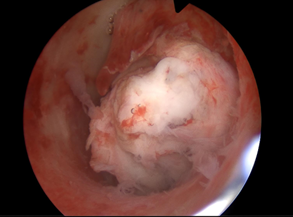

手术现场直击:

宫腔镜探头轻轻进入,那颗捣乱的肌瘤原形毕露——个头不小,像个饱满的“山竹”,大半个身子都“赖”在宫腔里。

医生稳准狠,用专用器械一点点把肌瘤剥出来。

手术超顺利!